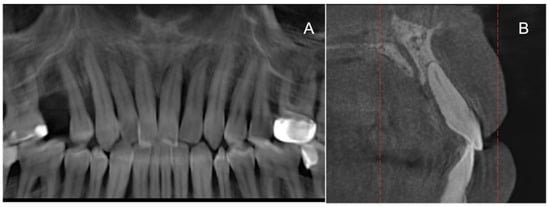

2. Materials and Methods

2.3. Surgical Treatment